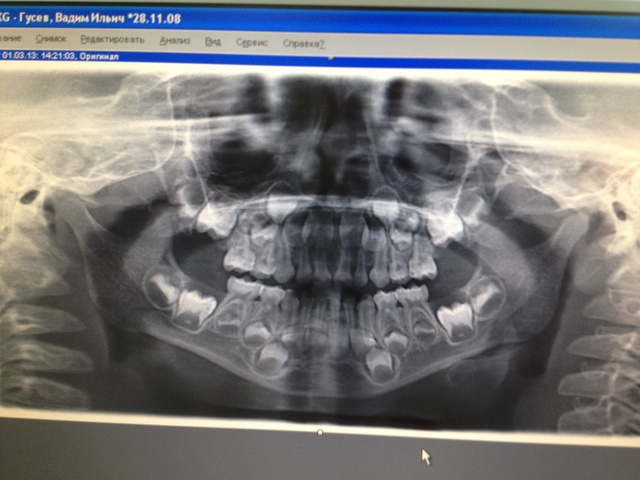

Сегодня сын на прогулке упал лицом и стал жаловаться на передние верхние резцы , что болят . Визуально передние резцы стали стоять неровно. Или правый ушел вперед или левый назад ..... В клинике сделали панорамный снимок сказали нет перелома.... Можете и вы посмотреть?

Вот увеличинла снимок:

Мне не нравится белая полоска у 61-62 зуба.....

Я бы сделала прицельный снимок левой стороны (61-62 зубы), мне тоже не нравится поперечная полоса, но, может быть, это артефакт?

На прицельном будет 100 процентов ясно!